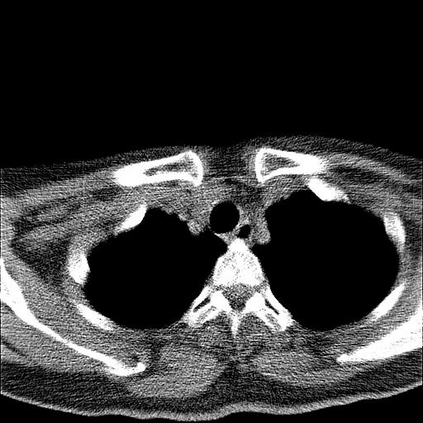

Low-Dose Computed Tomography (LDCT) technique, which reduces the radiation harm to human bodies, is now attracting increasing interest in the medical imaging field. As the image quality is degraded by low dose radiation, LDCT exams require specialized reconstruction methods or denoising algorithms. However, most of the recent effective methods overlook the inner-structure of the original projection data (sinogram) which limits their denoising ability. The inner-structure of the sinogram represents special characteristics of the data in the sinogram domain. By maintaining this structure while denoising, the noise can be obviously restrained. Therefore, we propose an LDCT denoising network namely Sinogram Inner-Structure Transformer (SIST) to reduce the noise by utilizing the inner-structure in the sinogram domain. Specifically, we study the CT imaging mechanism and statistical characteristics of sinogram to design the sinogram inner-structure loss including the global and local inner-structure for restoring high-quality CT images. Besides, we propose a sinogram transformer module to better extract sinogram features. The transformer architecture using a self-attention mechanism can exploit interrelations between projections of different view angles, which achieves an outstanding performance in sinogram denoising. Furthermore, in order to improve the performance in the image domain, we propose the image reconstruction module to complementarily denoise both in the sinogram and image domain.